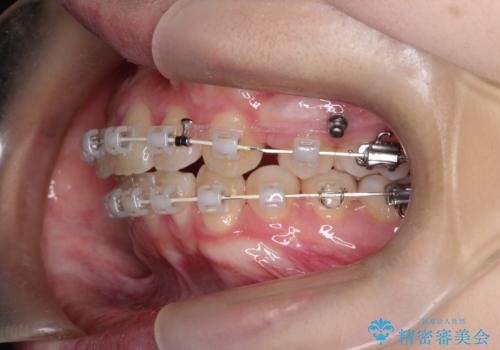

途中、矯正用のアンカースクリューを使うことで、最終的にきれいに前歯の真ん中を合わせることができました。

矯正用アンカースクリューを使用することで、歯の移動量をコントロールできるため、治療の仕上がりをよくすることができます。